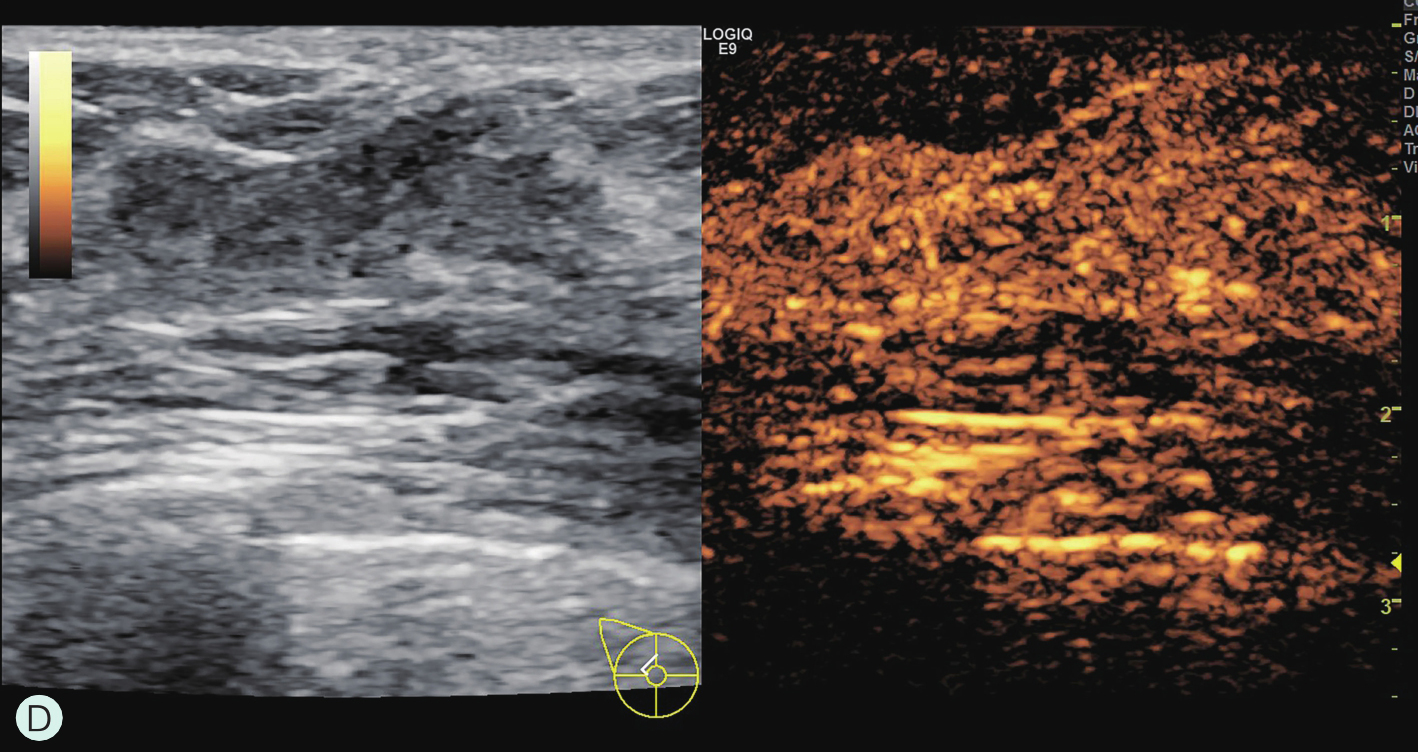

乳腺主要由胸廓内动脉、胸外侧动脉及肋间穿支动脉供血(图1-4-1A~图1-4-1C)。胸廓内动脉发自锁骨下动脉,在相应肋间胸骨旁发出分支穿过胸大肌,主要供应乳房的内侧部分血供;胸外侧动脉发自腋动脉第2段,穿过腋静脉深面,经腋窝沿胸小肌下缘走行,负责胸大肌、胸小肌、前锯肌及乳房外侧部分血供;另外,第3~5肋间动脉从各相应的肋间穿出,与胸外侧动脉及胸廓内动脉分支吻合,供应乳房下部分血供。上述三组主要动脉在乳房内又不断分支并相互吻合形成血管网,且走行自然连续,但缺乏类似于肝脏及肾脏有规律的血管分支树结构,同一女性双侧乳房或不同女性间都不相同,无固定分支规律可循(图1-4-1D)。

图1-4-1 乳腺血供与影像学

A.乳腺血供示意图;B.乳腺增强MRI造影血管图;C.乳腺增强MRI三维重建血管图;D.乳腺血管铸型解剖标本

1.胸廓内动脉;2.腋动脉;3.胸外侧动脉